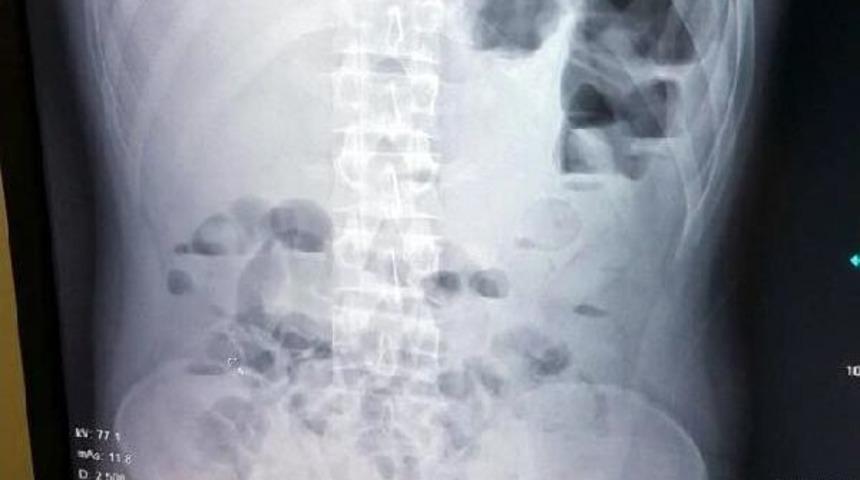

Gözetim altına alınan yabancı uyruklu kişinin çekilen röntgeninde, mide ve bağırsaklarında 54 yabancı cisim tespit edildi. Hastanede 2 gün gözetim altında tutulan kuryenin tuvalet ihtiyacını gidermesi sonucu 61 prezervatif içerisine paketlenmiş toplamda 1 kilo 37 gram eroin maddesi ele geçirildi.